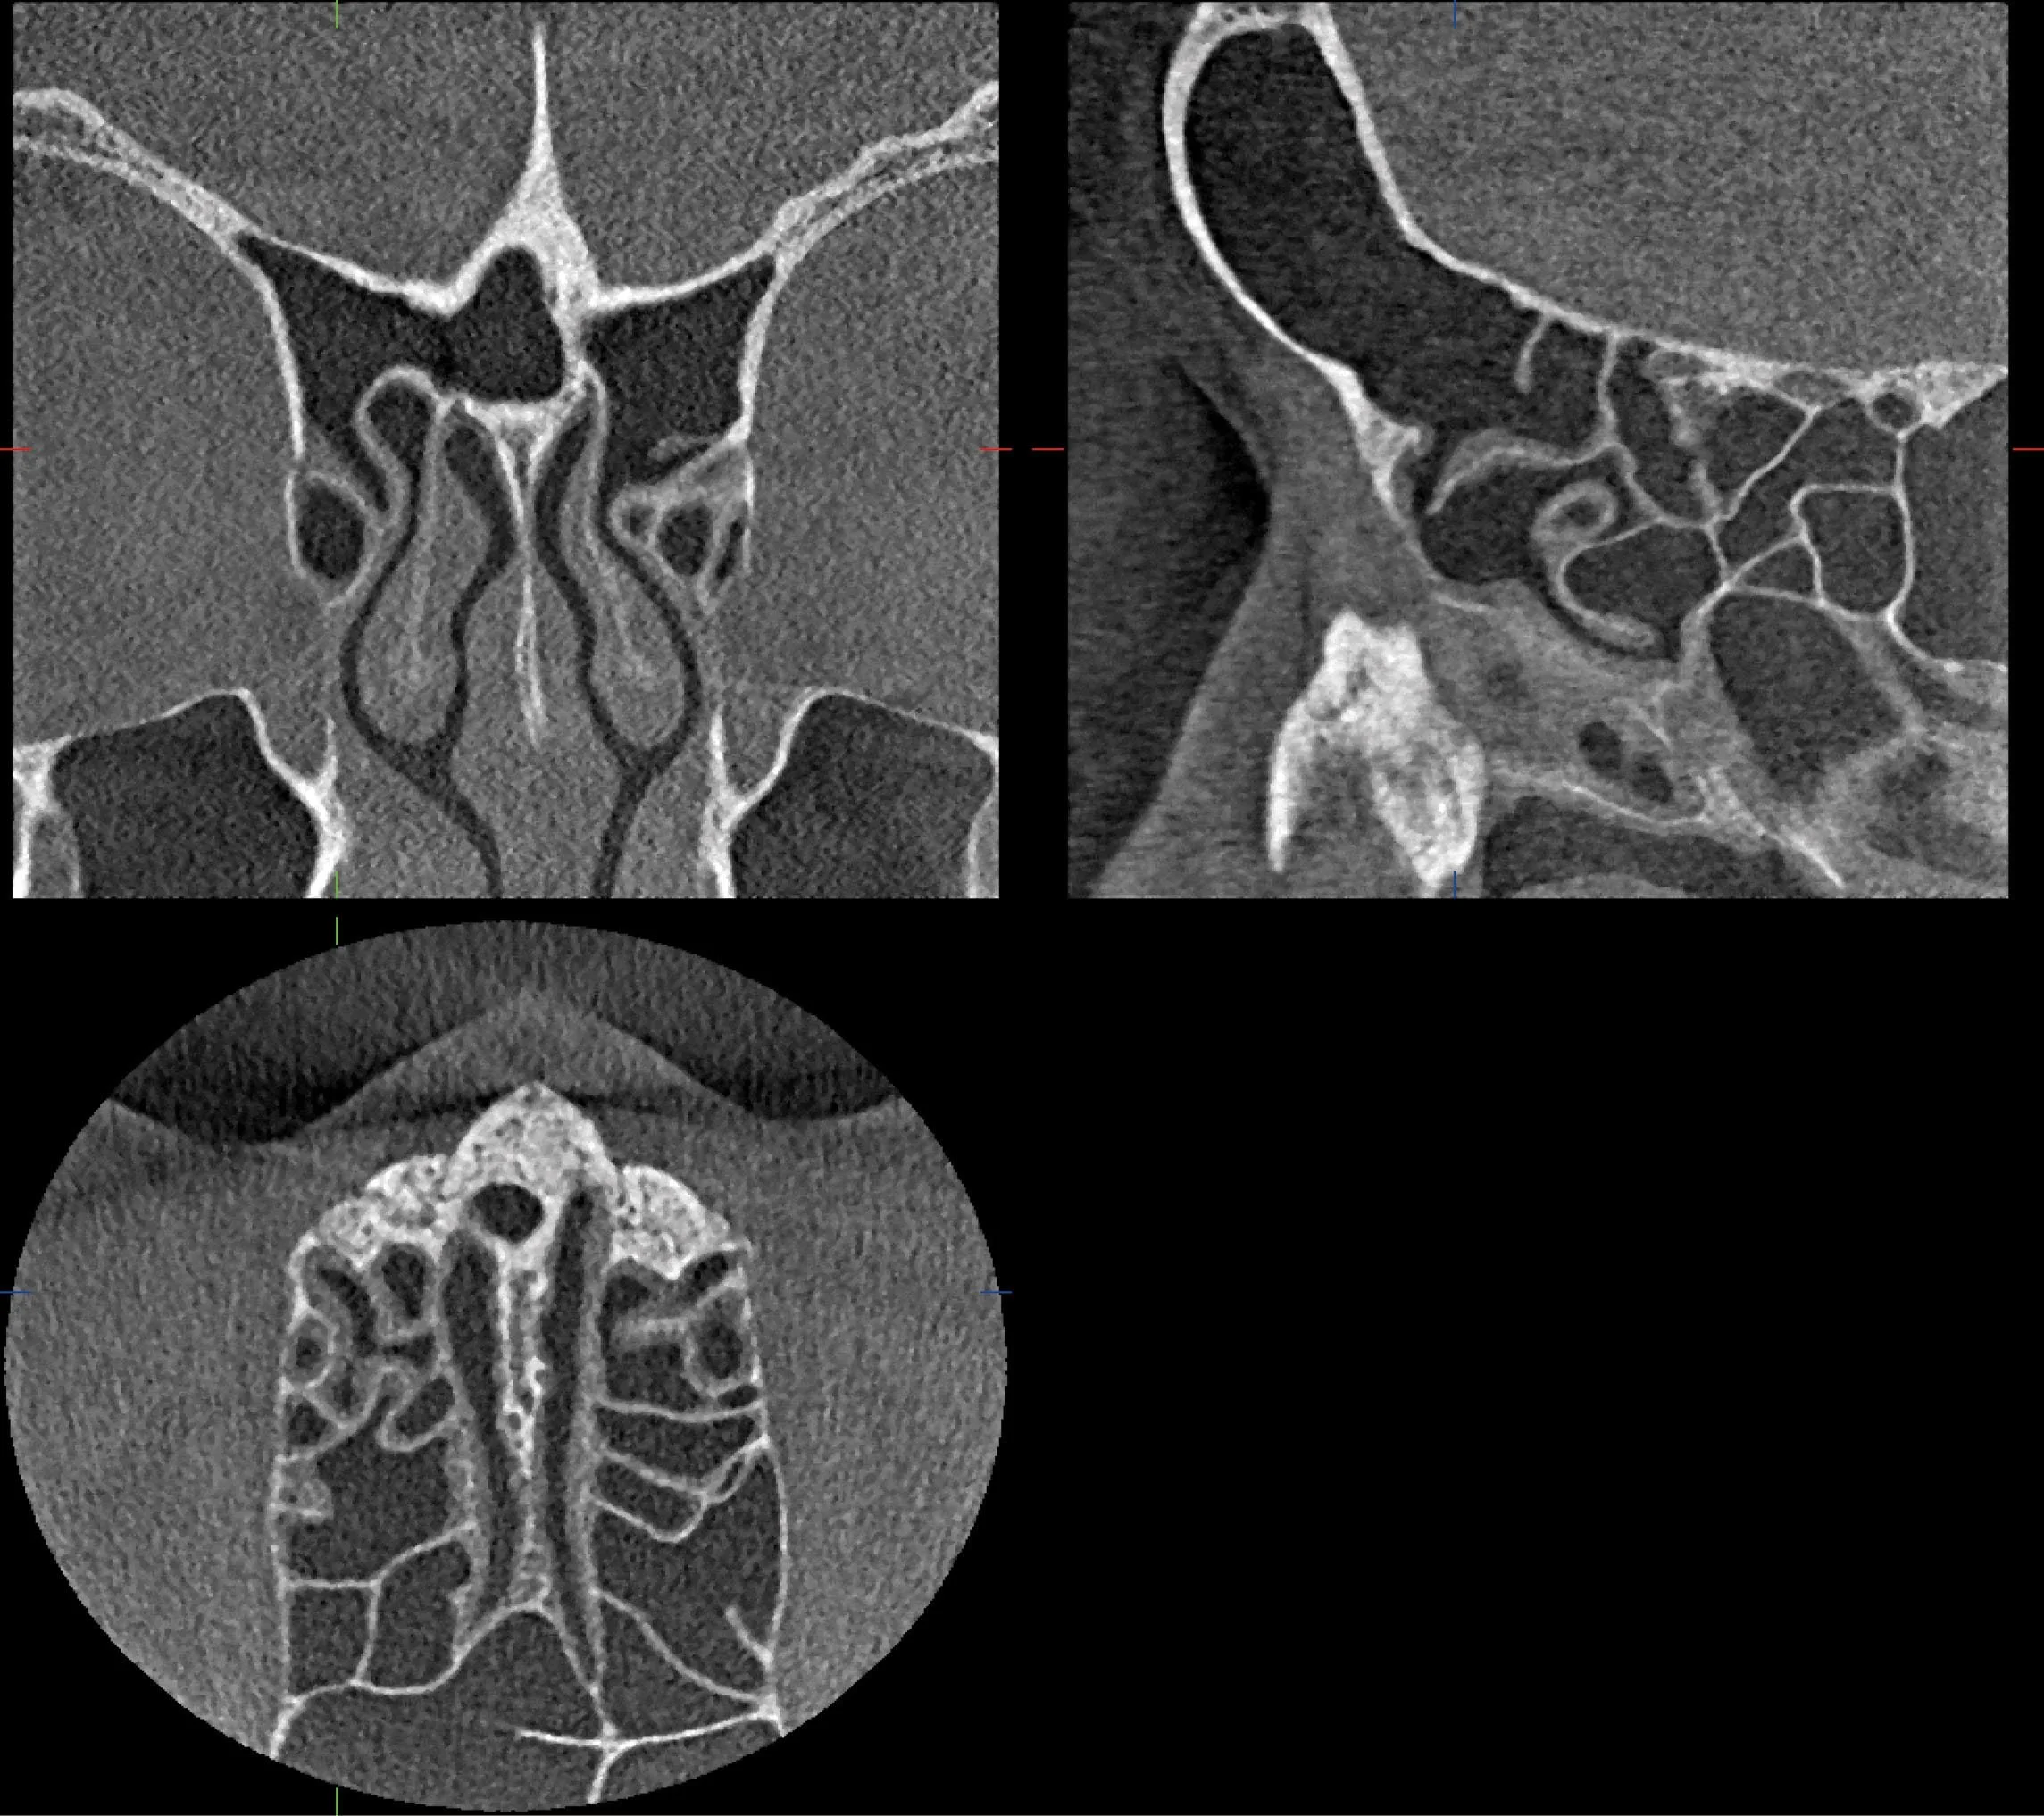

Con nuestros equipos podemos obtener imágenes panorámicas, de perfil y en 3 dimensiones con gran nitidez, gracias a su sistema innovador que sigue perfectamente la curva natural de tus dientes, consiguiendo ver toda tu boca de la forma más clara posible, enfocándonos solo en lo que realmente importa: diagnósticos mucho más precisos con la menor radiación necesaria.